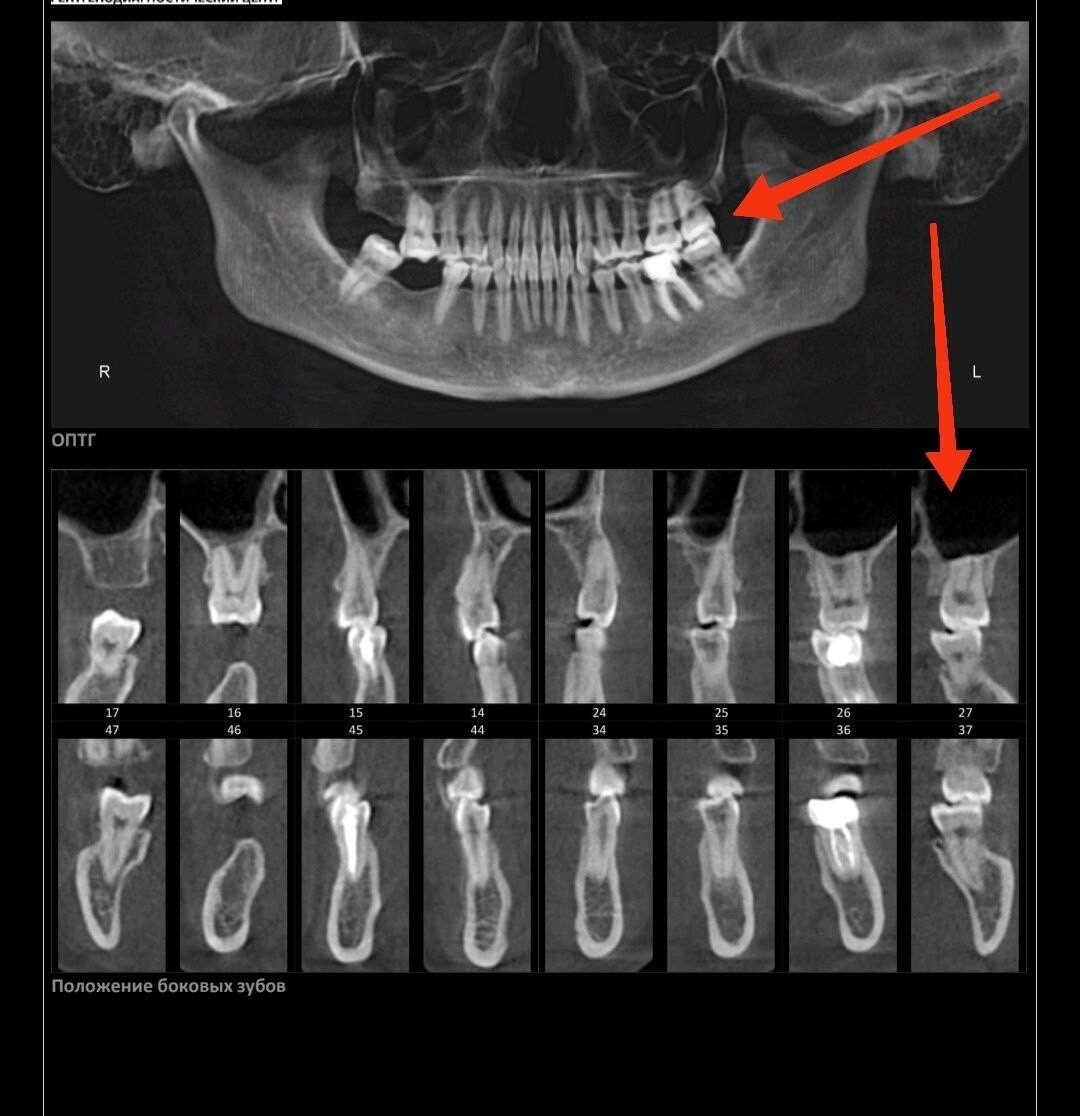

В чате курса девушка прислала снимки КТ стоя и МРТ лежа. Специалист сразу задала вопрос, что произошло, оказалось, просто положение тела разное.

К вопросу о том, почему нельзя регистрировать прикус лежа в кресле стоматолога, изготавливая в итоге под лежачее положение пломбы, коронки и прочие приблуды.

Это как и с зубами: лечить или сделать слепки удобнее, конечно, лежа - положение не имеет значения. Но именно для понимания истинной картины того, как челюсти и зубы стоят относительно друг-друга, требуется вертикальное положение.